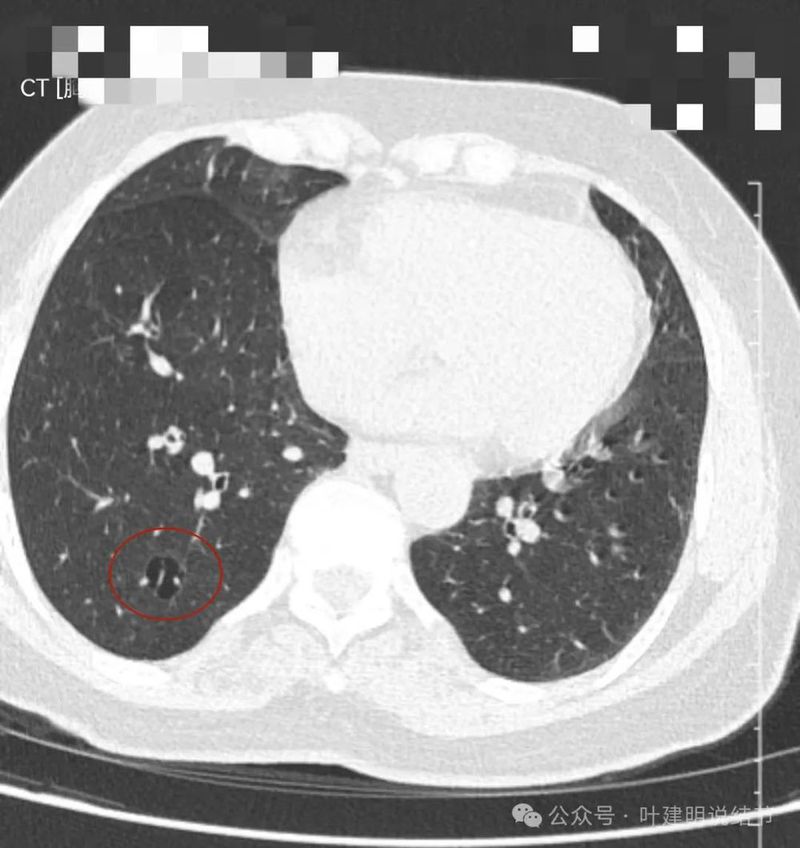

轴位病灶实性,分叶,膨胀!

病灶表面不平,有浅分叶,与膈肌之间有间隙。

与膈肌之间间隙明显,病灶实性,膨胀性明显,边缘相对较为光滑。

病灶浅分叶,膨胀性,周围有很淡的磨玻璃密度似的,这可能是检查时屏气屏得不太好的关系,不太符合混合磨玻璃结节的样子。

整体感觉较圆,膨胀性是明显的。膈肌有点被它顶过去的样子。

上图层面相对最大,感觉鼓鼓的。

边界与轮廓清。

上图显得膨胀感欠了点,但分叶与表面不平是明显的。

边比较为平直,密度仍实。

感觉两处不同的中心,如果连续层面看,应该是病灶不平的关系,与膈肌间仍有间隙,密度是实性的。

纵隔窗见病灶实性密度,与膈肌间有低密度线状间隙。

病灶密度稍不均。